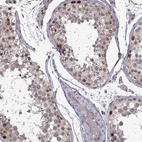

Immunohistochemical staining of human testis shows strong nuclear positivity in a subset of cells in seminiferous ducts.